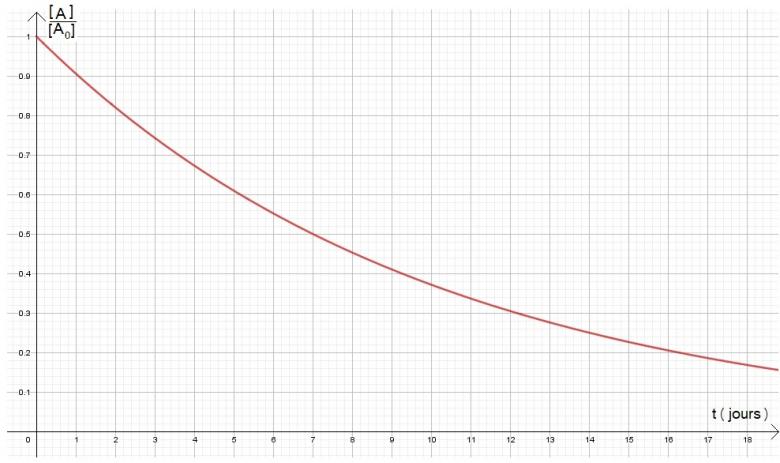

Ex: L'élimination de la digitaline administrée par voie intraveineuse suit une cinétique du premier ordre. Le temps au bout duquel la moitié du médicament est éliminé est de 7 jours. Calculer le temps nécessaire pour en éliminer 80 %.

Tu n'as plus qu'à calculer t pour [A] = 0,2[A_0]

Mais après je suis totalement perdu ... Le 0,2 correspond à quoi ? ^^

Ah je viens de comprendre d'ou vient le 0,2. C'est ce qu'il reste en digitaline non ?

Donc ça ferait ( 1 / (ln2 / 7) ) * ln (1/ 0,2) = 16,25 jours soit 16 jours et 6 heures